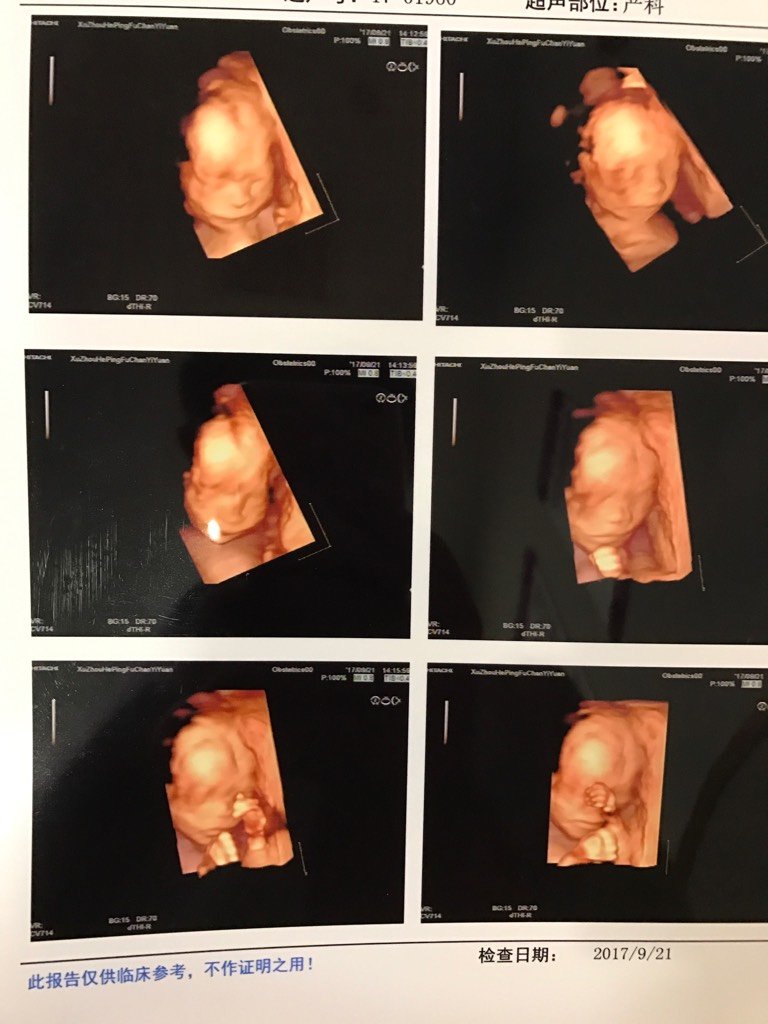

楼主152*****529_NbqX

宝宝8岁1个月5天 LV.4怎么感觉嘴巴那么大[笑眼]

宝宝8岁1个月5天 LV.422+1周呢

孕40周+0天 LV.9因为他现在还没长好 所以看着嘴巴比较突出 我家这个也是 当时我说我和老公嘴巴那么小他嘴巴怎么那么大 医生这样说的

152*****529_NbqX:怎么感觉嘴巴那么大[笑眼]

宝宝8岁1个月5天 LV.4是这样就好了!我还说来,我家里嘴巴没有大的,老公家里那边也没有,嘴巴那么大,不好看呀

娜娜1994:因为他现在还没长好 所以看着嘴巴比较突出 我家这个也是 当时我说我和老公嘴巴那么小他嘴巴怎么那么大 医生这样说的

宝宝8岁1个月5天 LV.4哎,发给我妹看,她说嘴巴像蛤蟆[升起][升起][升起]

孕40周+0天 LV.9现在小 所以嘴巴和头是比较突出的

152*****529_NbqX:是这样就好了!我还说来,我家里嘴巴没有大的,老公家里那边也没有,嘴巴那么大,不好看呀